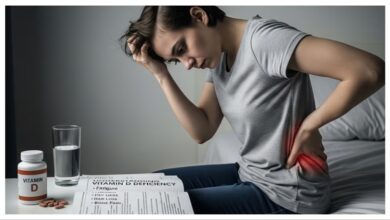

Vitamin D3: शरीर के लिए जरूरी है ये विटामिन, कमी होने होता है ये नुक्सान

स्वस्थ रहने के लिए विटामिन डी बहुत जरूरी है। विटामिन डी केवल एक विटामिन नहीं है। यह पोषक तत्वों का…